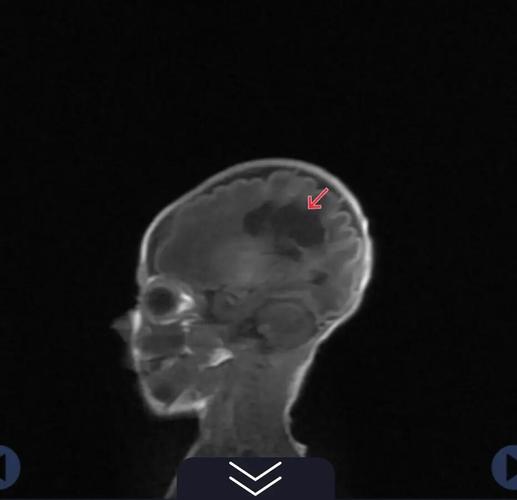

- 磁共振扫描:

- T1加权像(T1WI):呈低信号(很黑)。

- T2加权像(T2WI):呈高信号(很白)。

- 液体衰减反转恢复序列(FLAIR):呈高信号,能更好地显示与脑脊液区分开来的病灶。

- 特征性表现:软化灶的信号特点与脑脊液几乎完全一样。